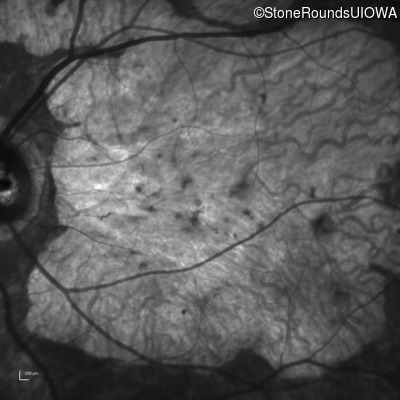

Infrared Fundus Photograph - Left - 10/125 +1 sc

Exemplar